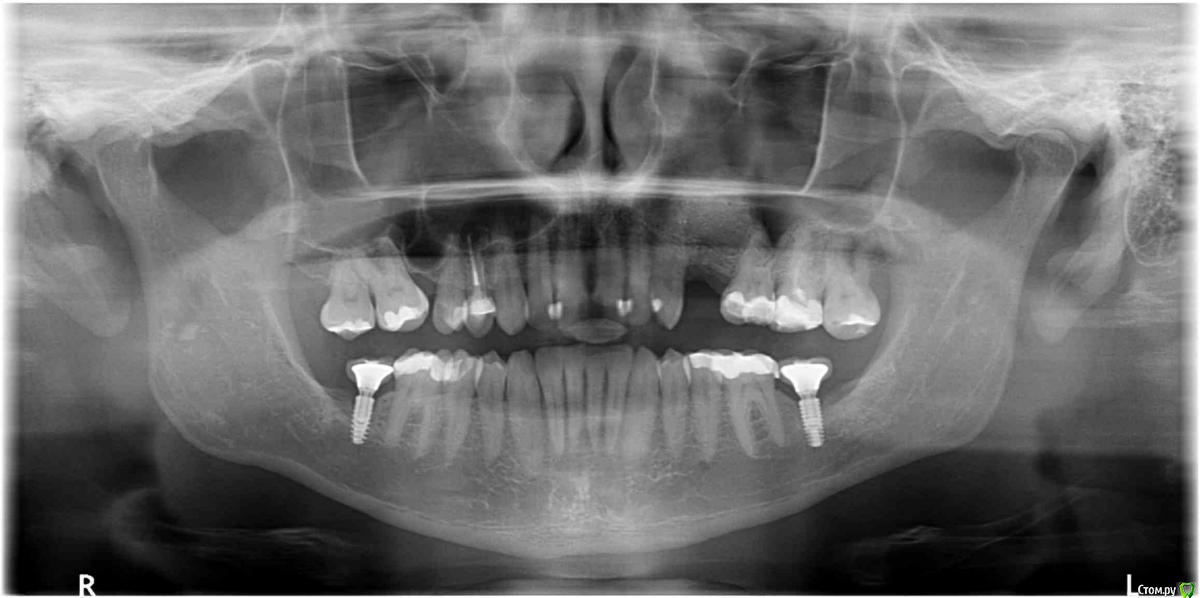

tonkin Опубликовано 9 января, 2017 Поделиться Опубликовано 9 января, 2017 Помогите определиться с числом имплантов. Отсутствуют 2 верхних зуба (в красном квадрате на пано). Расстояние между корнями ~ 16.5 мм. Вопрос следующий, какой вариант лучше (оба после планируемого синус лифтинга): 1) поставить 1 толстый имплант по центру с двойной коронкой, чтобы изобразить 2 зуба под улыбку. Тут смущает то, что в прошлом году уже такой вариант делали. Имплант расшатался за 3 месяца, и выпал (снимок импланта был сделан за 2 месяца до паноромного, где импланта уже нет). Вероятно, что имплант был коротковат для такой нагрузки (да и кости мало), и если сделать лучше, то будет держать двойную коронку нормально. 2) второй вариант - 2 тонких импланта с индивидуальными коронками, но места маловато (4 мм + 3 мм + 4 мм + 3 мм + 4 мм = 18 мм < 16.5 ). То есть все очень впритык. Смущает значительная добавочная стоимость, но с другой стороны, шатающегося импланта как в первом случае уж очень хочеться избежать. Мнения? И если стоимость - не вопрос, то будут ли 2 импланта лучше 1-го ? Дополнительный вопрос - как выглядят 2 нижних импланта на предмет качеста кости. Имплантам - 13 месяцев, коронкам - 7. Эти вроде пока держатся (тфу-тфу). Заранее благодарю за консультацию! Ссылка на комментарий

tonkin Опубликовано 6 июня, 2018 Автор Поделиться Опубликовано 6 июня, 2018 Вот еще 2 пано, с наращенной костью до имплантов, и после, когда уже все зажило. Ссылка на комментарий